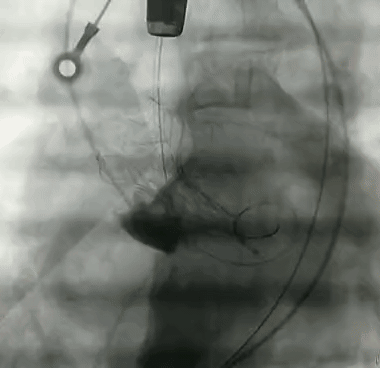

窦部造影

球囊预扩

VitaFlow#27 瓣膜定位

瓣膜释放

释放完成,后扩改善形态

形态良好,轻度瓣周漏

术后压差为8mmHg